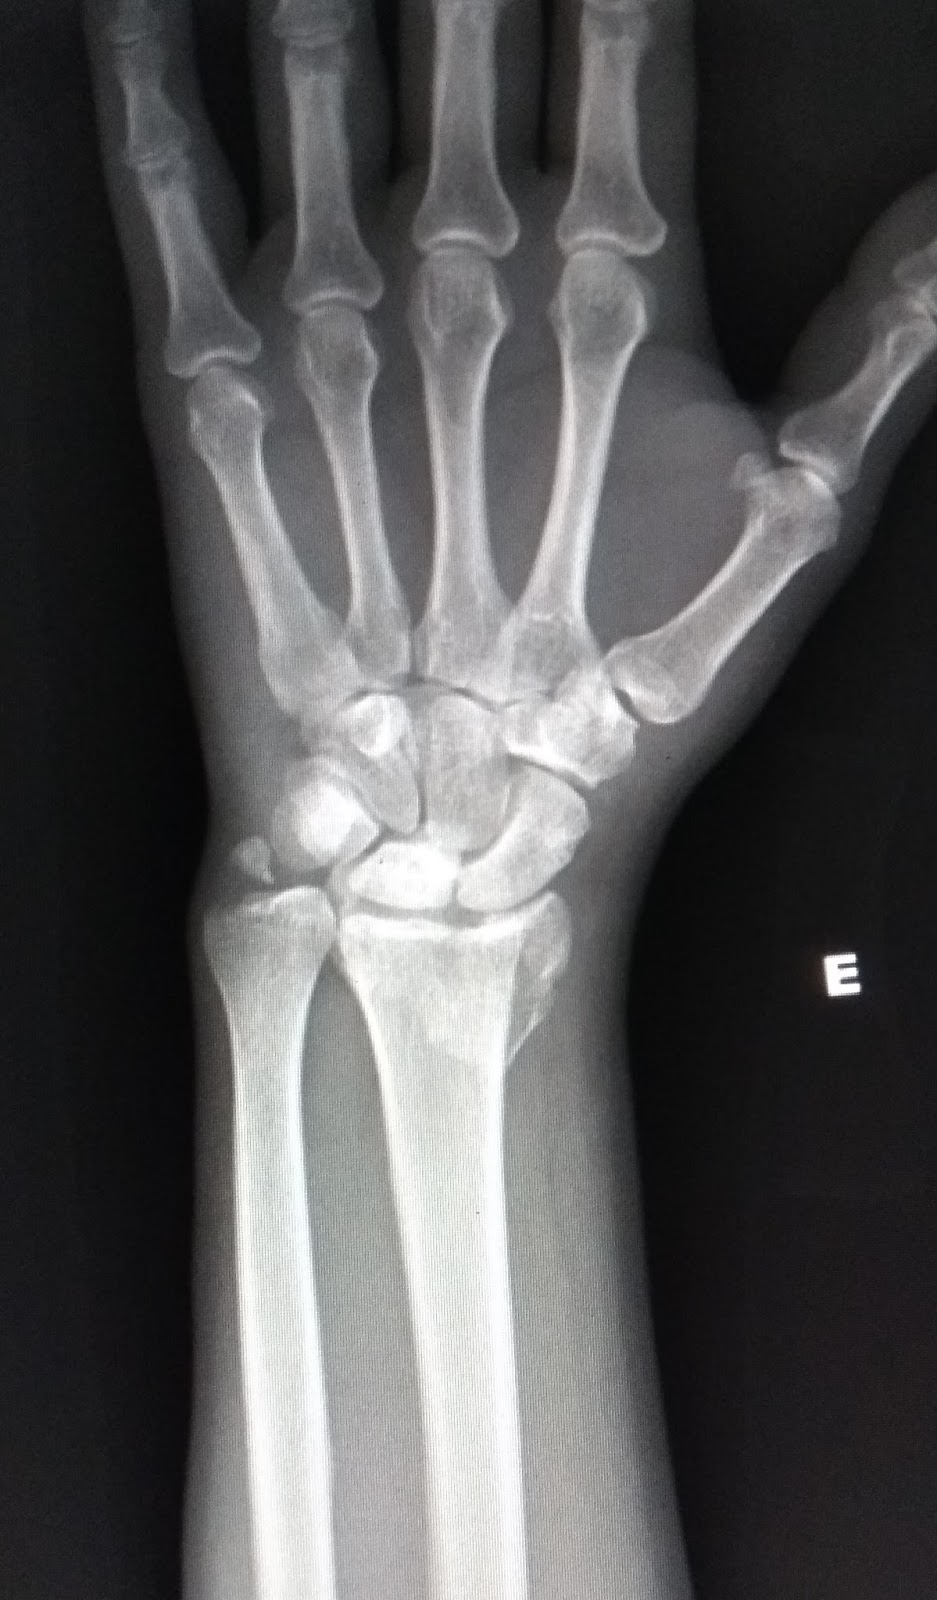

A fratura de rádio distal é uma das mais prevalentes entre as fraturas de punho, ocorrendo principalmente em casos de trauma de alta energia, em indivíduos jovens, e baixa energia, em idosos, em que o indivíduo cai no chão com a mão espalmada. Trata-se de um problema relativamente comum em crianças, especialmente em decorrência de.. Em geral, as fraturas da cabeça do rádio resultam de queda sobre o membro superior em extensão, e podem ser difíceis de ver nas radiografias. (Ver também Visão geral das fraturas .) A cabeça do rádio é palpável na porção lateral do cotovelo como uma estrutura que se rotaciona durante pronação e supinação e que se articula com o.